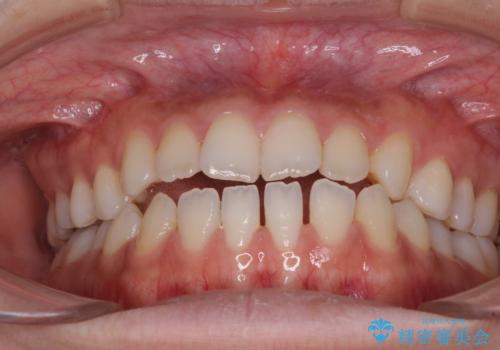

舌突出癖で口元が開いてしまう 舌トレーニングを行ったインビザライン矯正

- 前歯の上下スペースと前歯の隙間を気にして来院された患者様です。

インビザラインにより上下の前歯の隙間を閉じていくこととしました。

上下の隙間に舌が入り込むことが、すきっ歯やオープンバイトの原因であったため、舌の筋肉のトレーニングも並行して行い、後戻りの抑制を図りました。